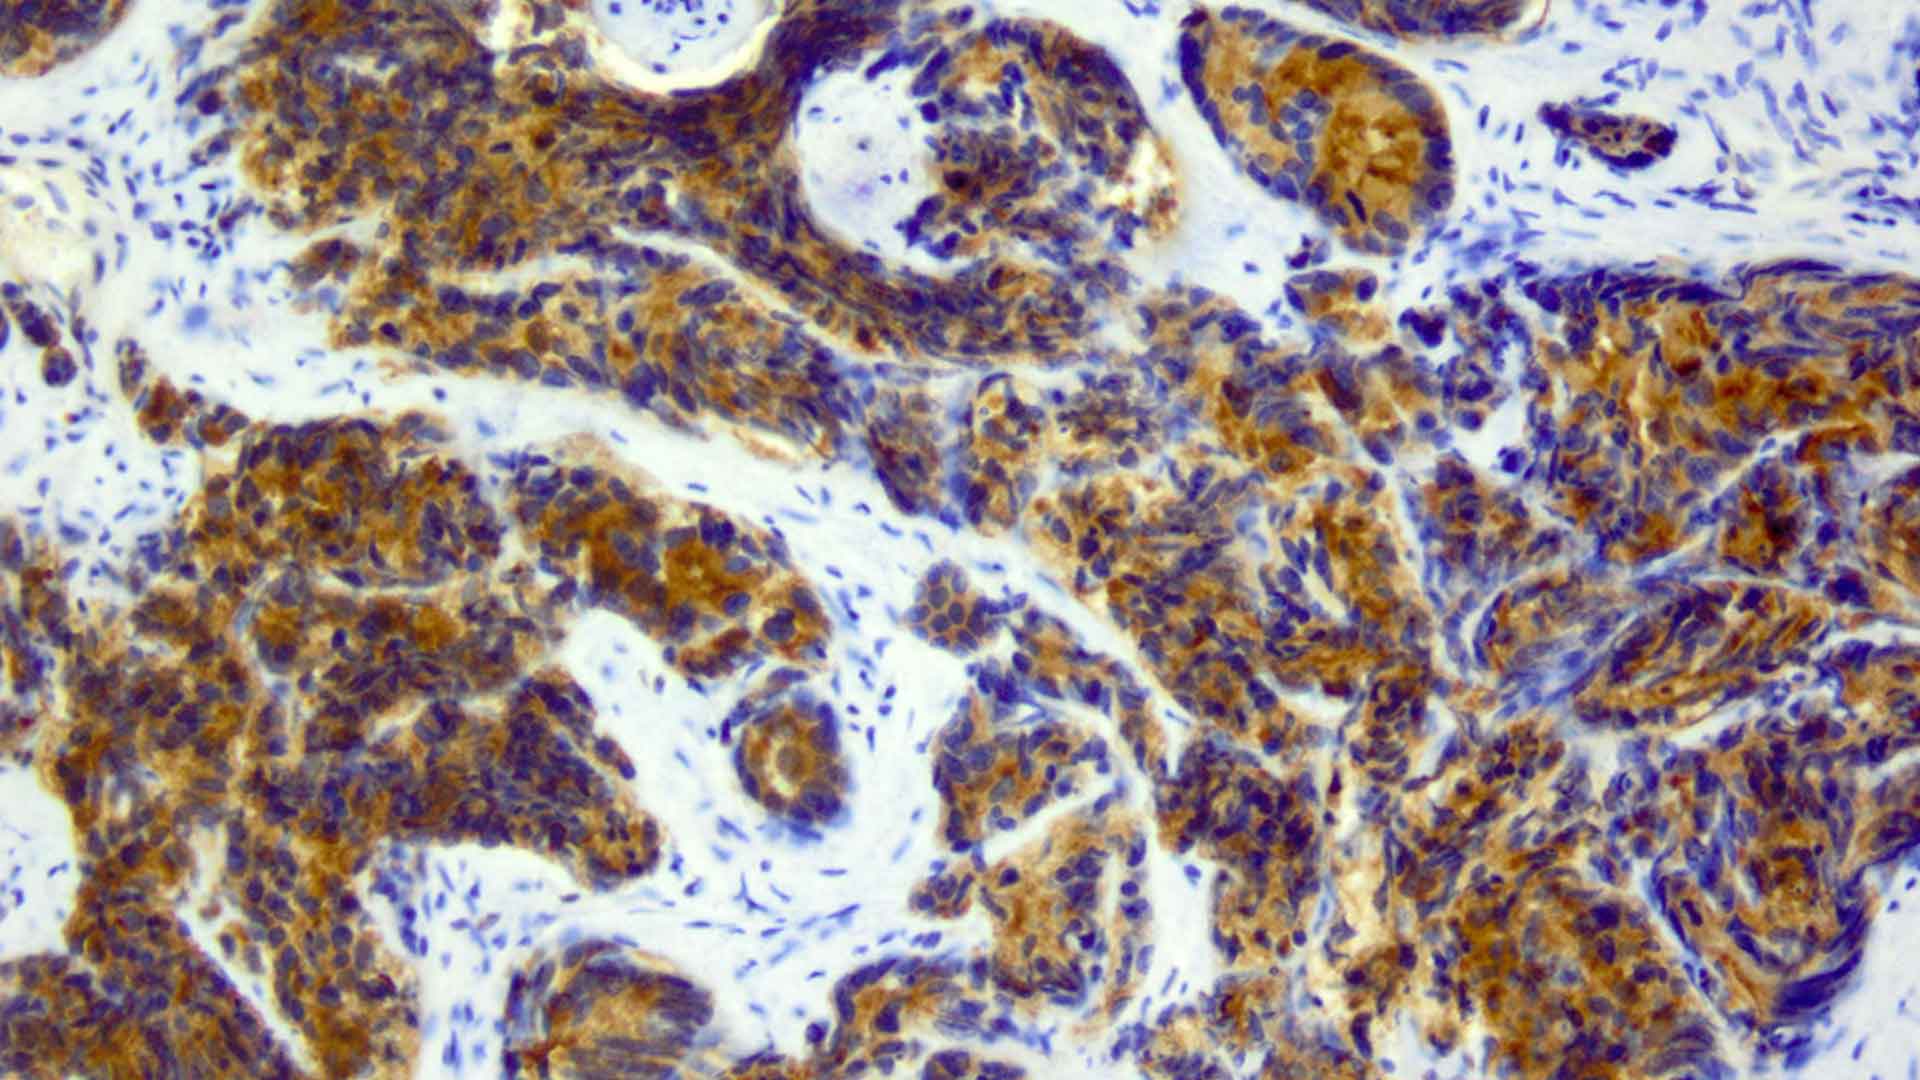

- HIFU (Fokale Therapie): Mittels gebündelter Schallwellen wird der Tumorherd, der die Blasenwand bedroht, auf über 80 Grad erhitzt. Die Krebszellen werden punktgenau zerstört, während das umliegende Gewebe geschont bleibt.